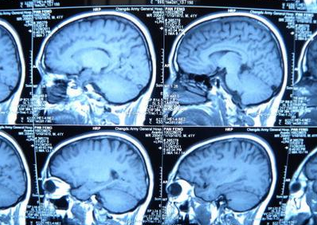

若怀疑自己患上了脑梗,那么患者应该到医院做哪些检查,进一步了解病情呢?脑梗由于是一种脑部疾病,并且这种疾病的并发症较高,因此,我们在做检查时要注意多方面因素.今天台州黄岩新安康复医院专家给我们介绍脑梗应该做哪些检查?

脑梗塞的检查项目如下:

1、检查是否有缺血性梗死或出血性梗死改变,合并出血性梗死高度支持脑栓塞.许多病人继发出血性梗死临床症状并加重,发病3~5日内复查可早期发现激发梗死后出血,及时调整治疗方案.另需观察颈动脉狭窄程度或闭塞。